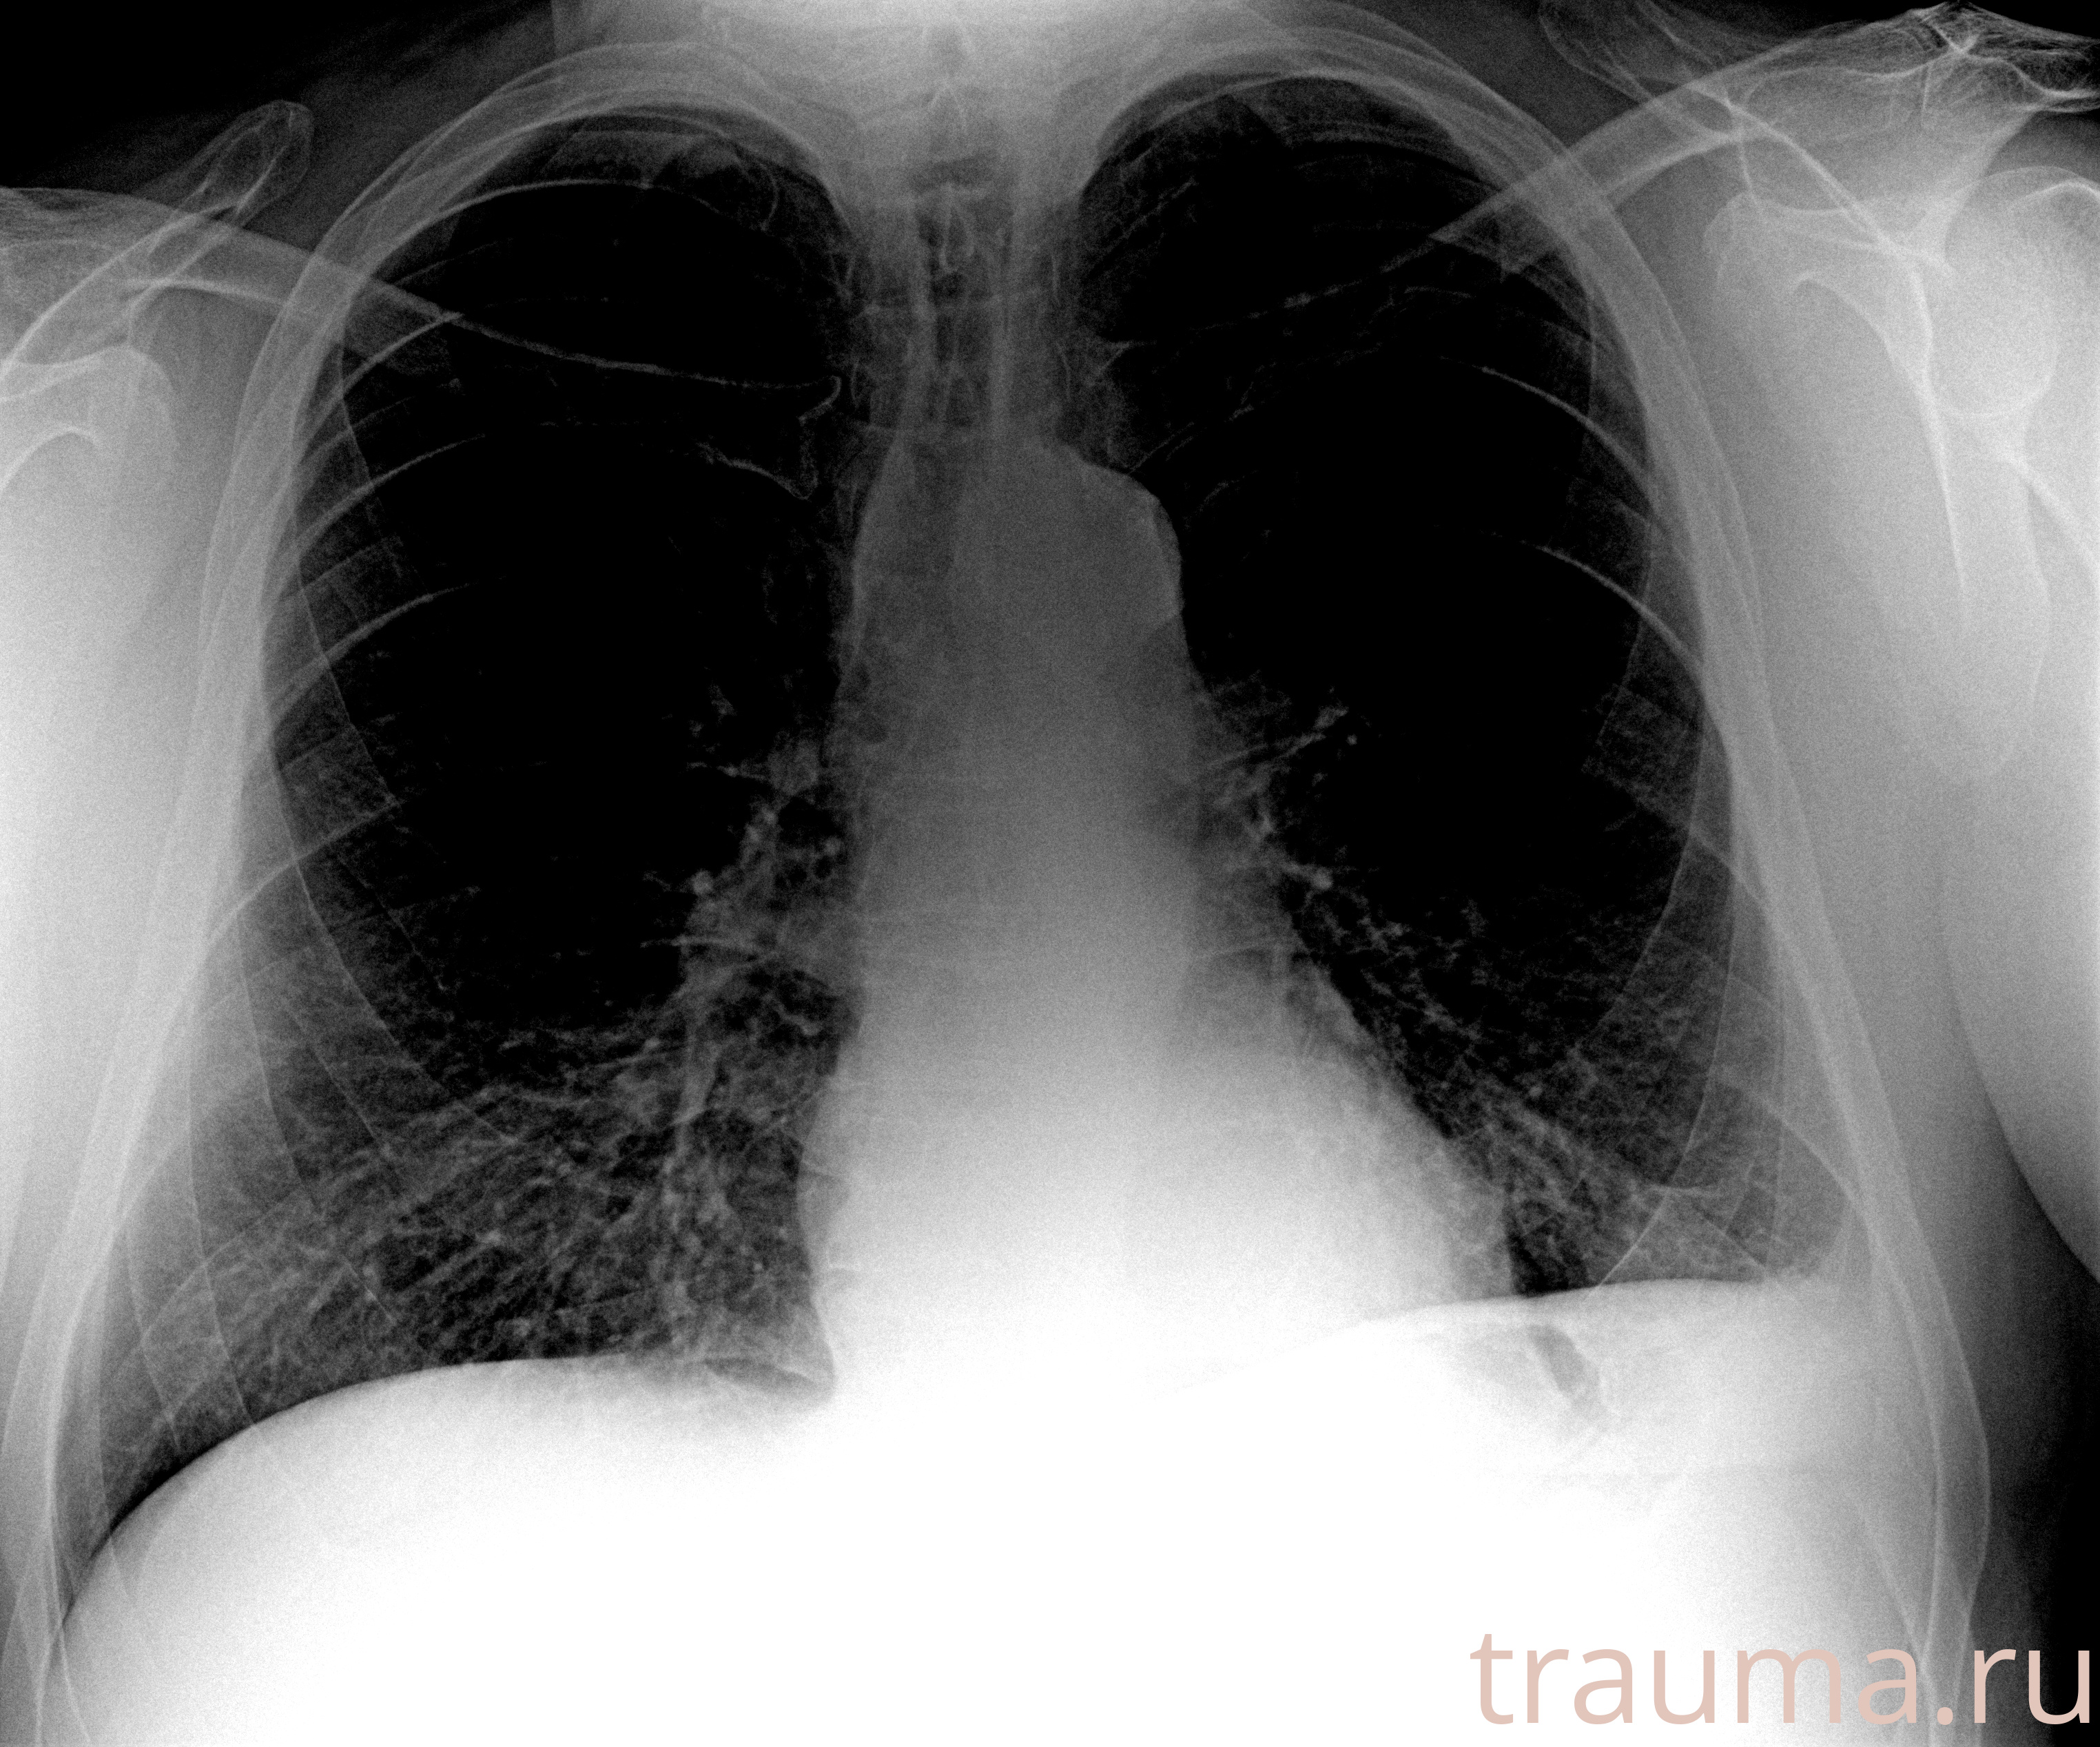

Рентгенограммы

Рентген на дому: по вашему адресу приезжает врач-рентгенолог, травматолог-ортопед с мобильным рентгеновским аппаратом, проводит диагностику травмы или заболевания, делает необходимые рентгенограммы, дает рекомендации по дальнейшему лечению. Получить качественные снимки в домашних условиях возможно благодаря уникальной методике, разработанной МосРентген Центром для института  Склифосовского

при переломе шейки бедра и пневмонии от компании МосРентген Центр - партнера Института имени Склифосовского